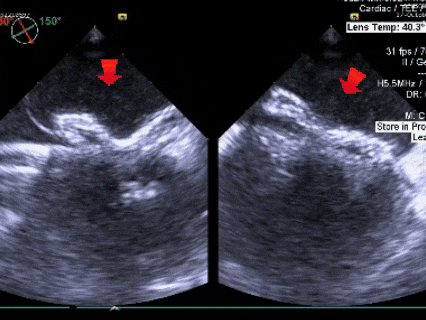

术中复测

测量膨出瘤基底宽19.61mm,深7.00mm

房间隔总长44.22mm,缺损大小14.80mm

超声可见房间隔连续中断,彩色多普勒可见过隔血流

三维下可见房间隔缺损